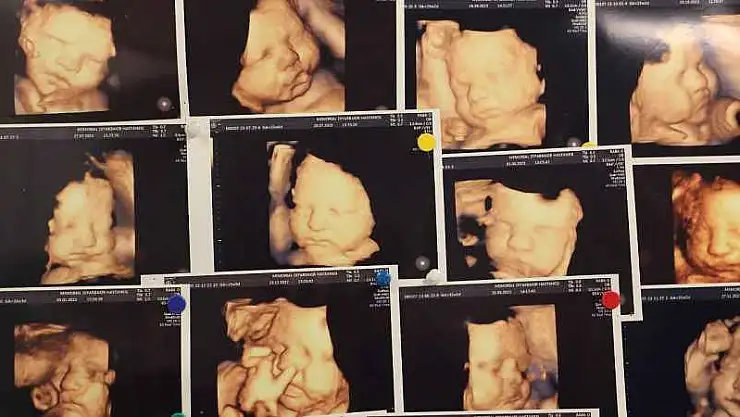

Tıbbi literatürde abortus yani Düşük olarak tanımlanan gebelik kaybı, bebeğin 500 gram ağırlığına ulaşmadan veya 20'inci haftadan önce çeşitli sebeplerden ötürü gebeliğin sonlanması anlamına geldiğini açıklayan Dr. Evsen, genelde en sık ilk 3 aylık dönemde görülebilmekte olduğunu dile getirdi.